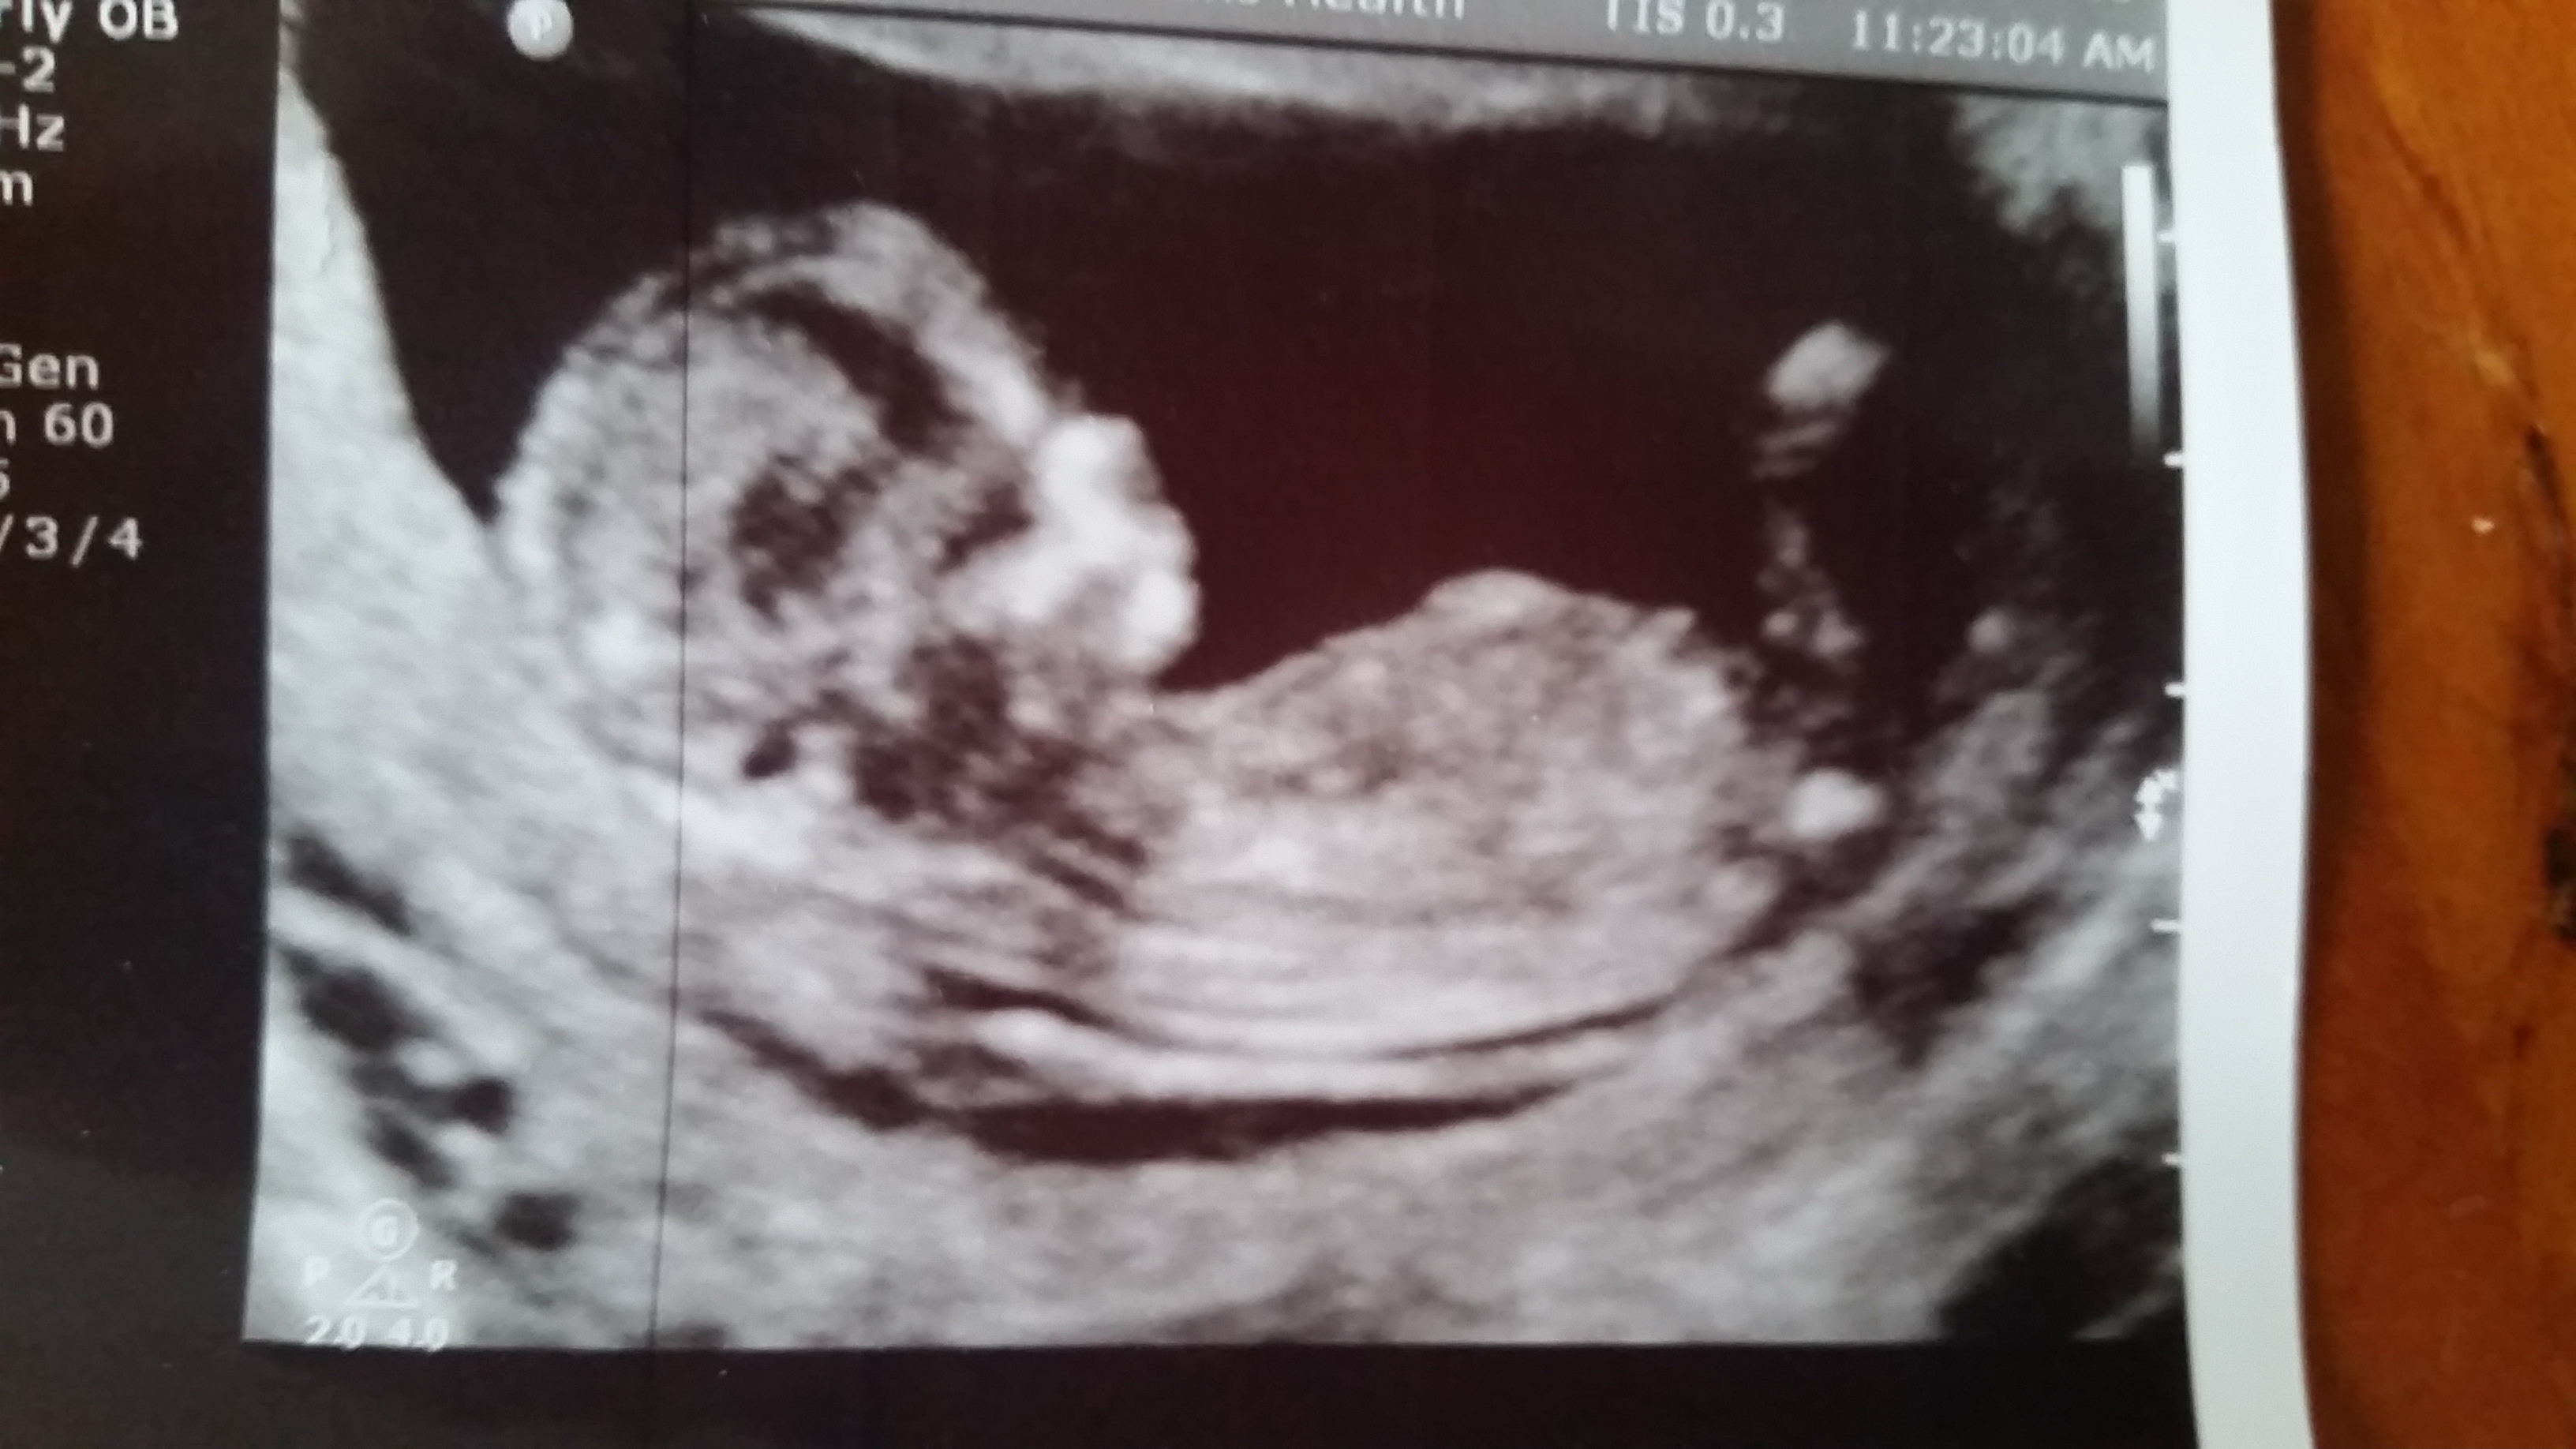

The tech refused to give me a guess, said she saw nothing between the legs, but at 12 weeks 3 days there wouldn't be anything anyway (?). This is the best shot I have. Attachment 27927

I don't see a clear nub and it's a little too early anyway. Sorry xx Goodluck!

You should put all pics you have of full body profile. No nub visible on this one.